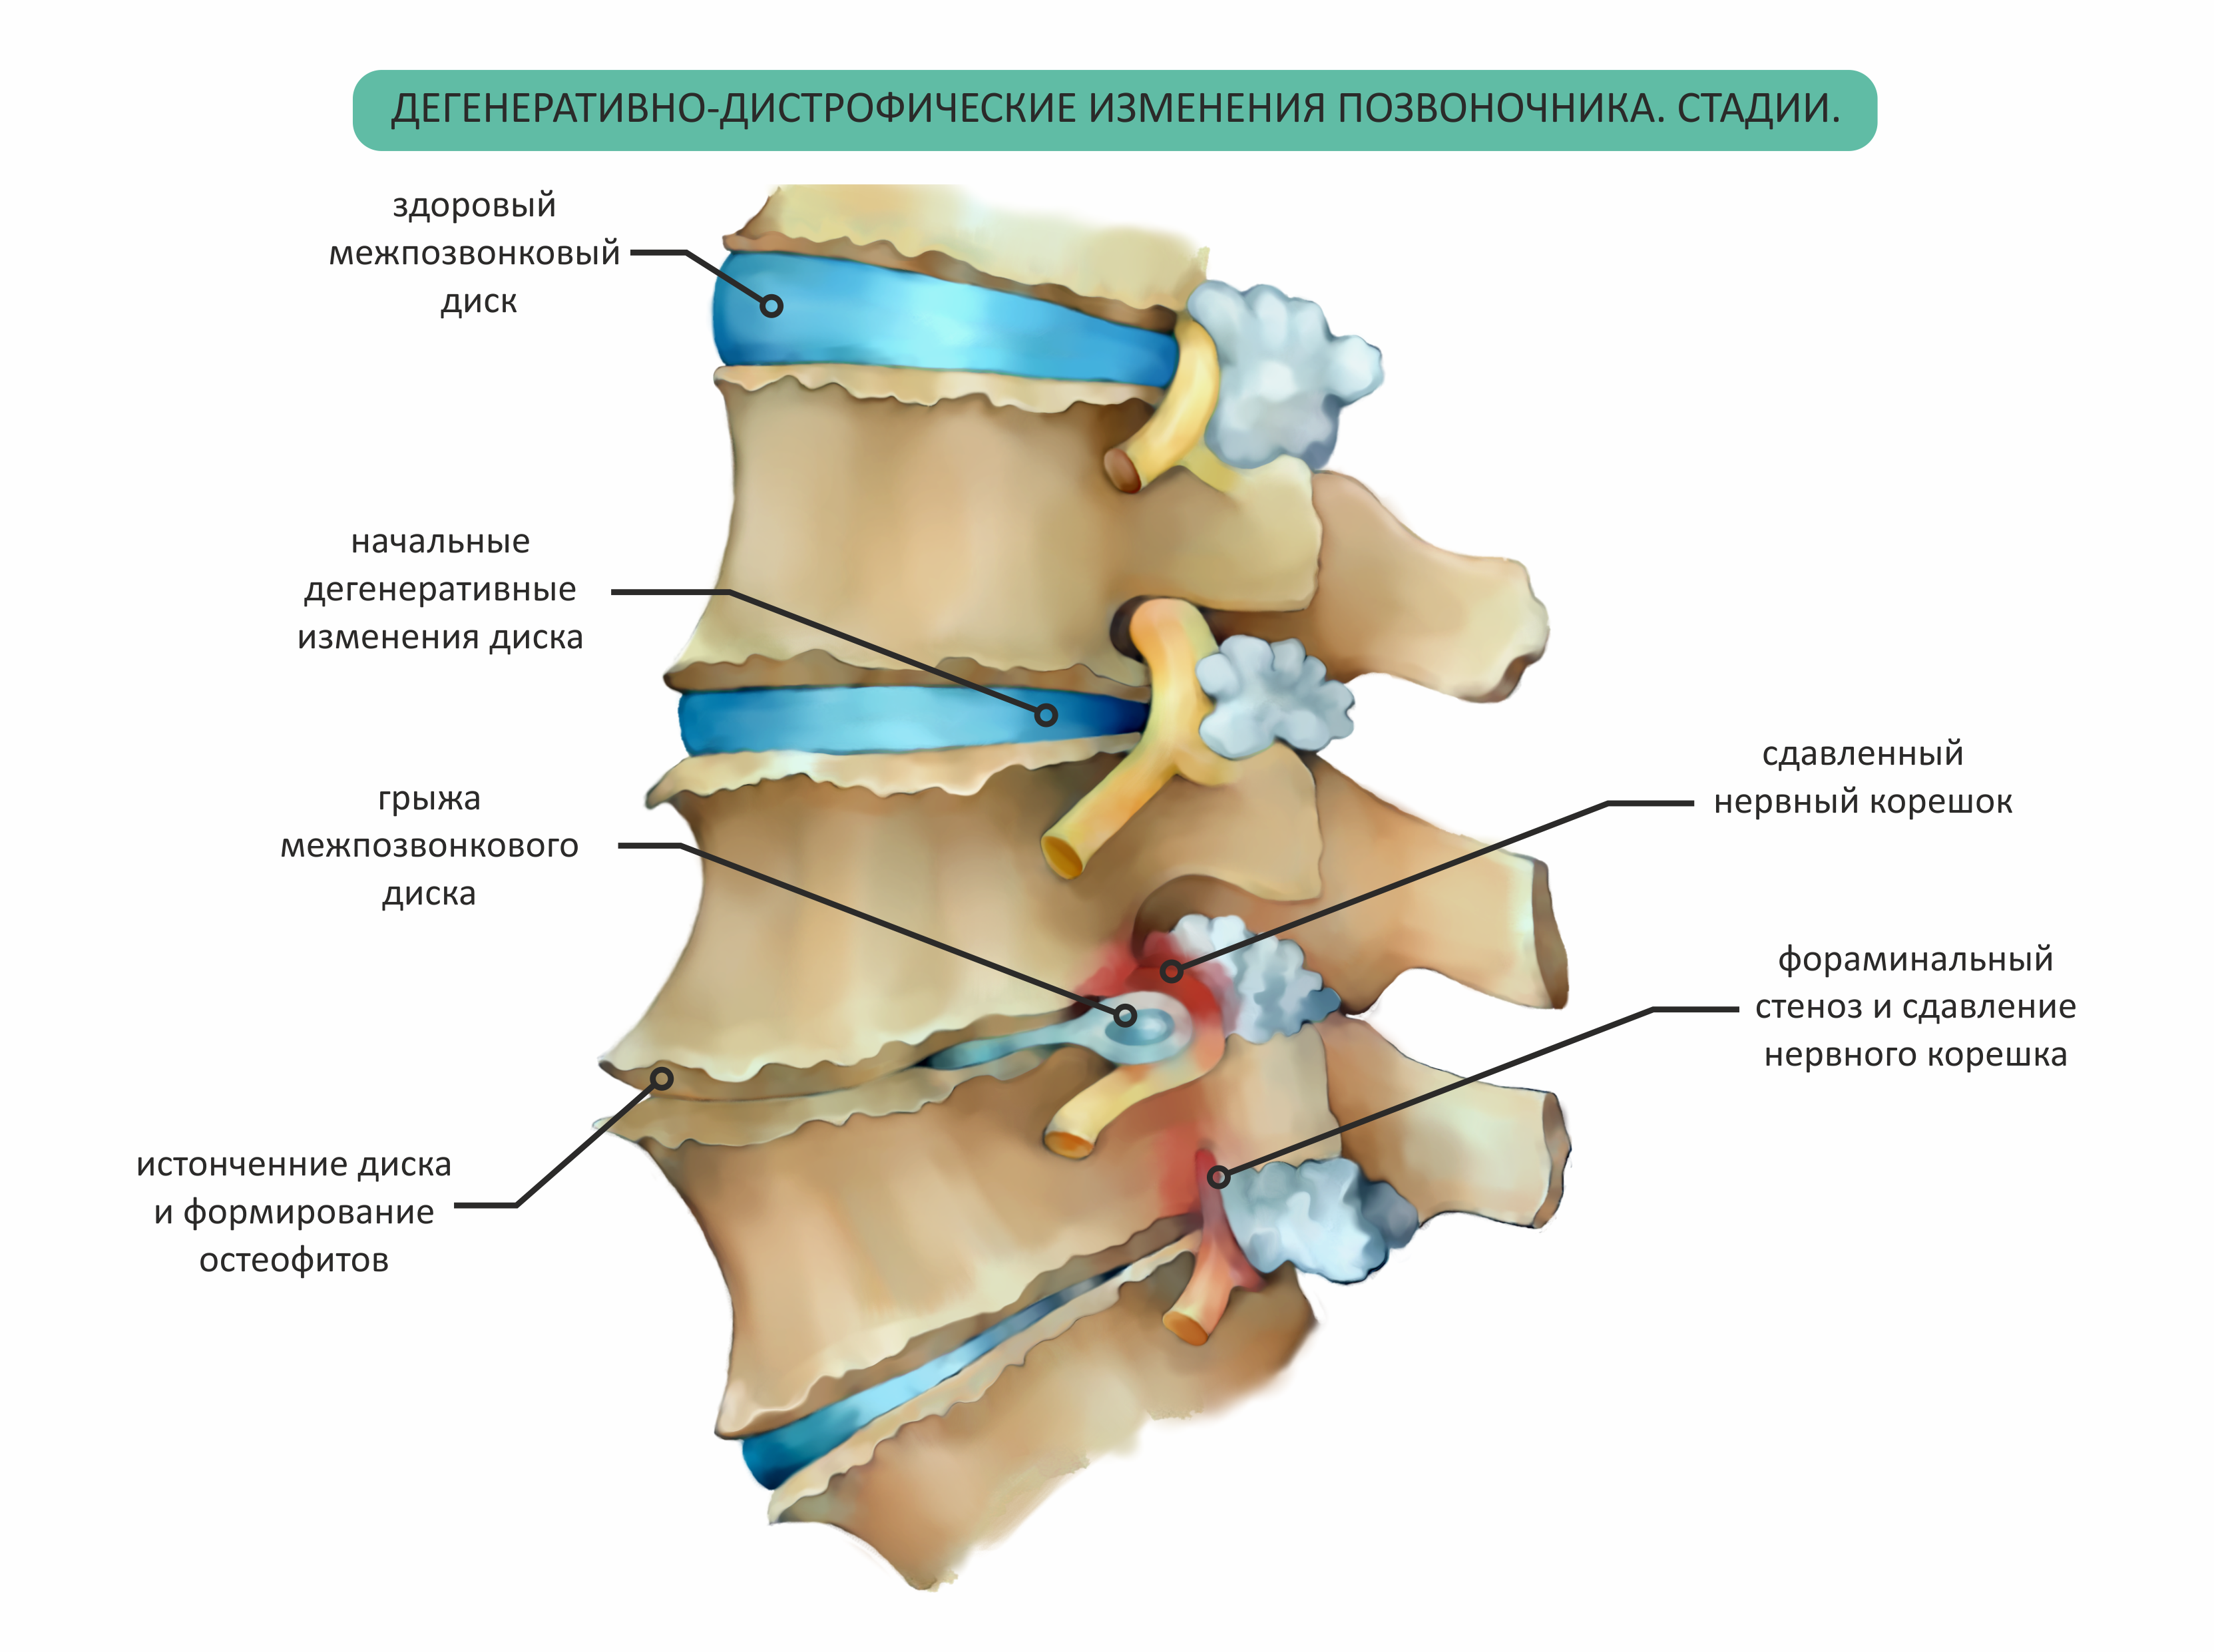

Мрт картина дегенеративно дистрофических изменений пояснично крестцового отдела позвоночника